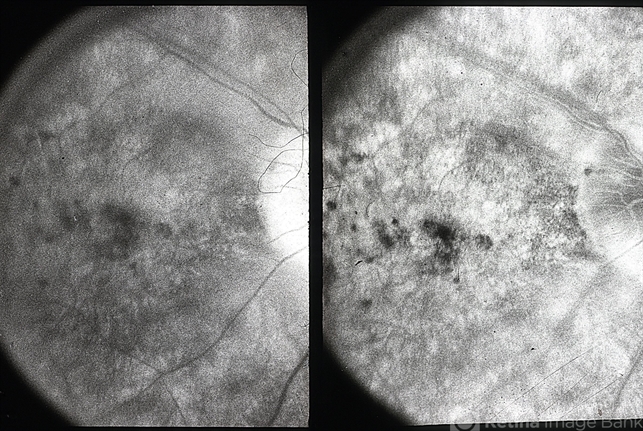

- non-staining cystoid macular edema (CME)

- FA of OD with RPE mottling at macula with no late leakage (possibly an eye with RP).